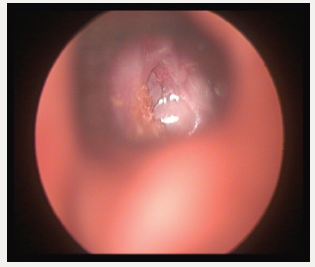

Persistent fluid in the middle ear causes not only reduced hearing, can go in for poor scholastic performances, speech-language development also. In long standing effusion, structural damage of the tympanic membrane (T.M) can go in for atelectasis, adhesion, ossicular damages, retraction pocket, and finally cholesteatoma. Stuart Mawson had described many of these complications after a long term follow up 129 glue ear cases [2]. Auto inflation and treatment URTI is the only treatment required. But the child should not sniff in. He should learn how to blow the nose correctly by occluding ne side first and then the other side, not two sides together (Figure2). Otovent is a rounded plastic balloon with a plastic nose piece. When the balloon is inflated auto inflation take place [3]. Even though the condition is considered self-resolving, since URTI is very frequent in childhood, by the time one incidence of OME is coming down, another URTI may start and the middle ear goes back to the previous stage. OME being a silent condition, many of the children present only in the late stages of the spectrum of the disease. By that time, irreversible damages might have taken place. Experimental studies in Chinchillas have demonstrated that the relationship between the time of evolution of effusion and structural changes of mucoperiosteum are related [4]. In this context, we should regularly follow up patients who are having OME and likely to have OME because of very frequent URTI (Figure3). If there is a structural damage tympanostomy must be done. Further episodes of URTI must be treated promptly (Figure4). The update of guidelines points out that under the age of 4 years adenoidectomy must be combined only in children having nasal obstruction or chronic adenoiditis. Above 4years adenoidectomy can be combined. It is learned that earlier, there was an epidemic of tympanostomy in U.K. [5].

Figure 2:Glue ear with atelectasis.